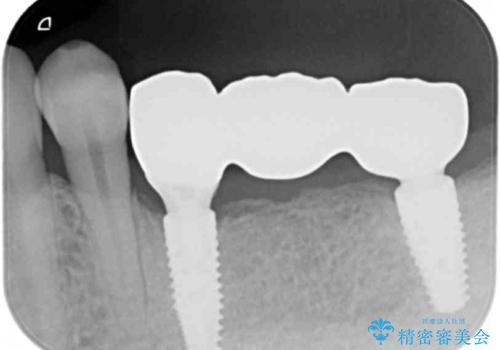

臼歯部インプラント・再補綴

- 失ってしまった左下の奥歯にインプラント治療を受けたいと来院されました。

左下の欠損部には強度・表面性状に優れるストローマン社製インプラントを埋入し、合わせて噛み合う上顎の歯もクラウン再補綴による整備を行い安定した咬合関係の構築を目指します。

- 122.1万円(仮歯×5・ストローマンインプラント×2・アバットメント×2・ジルコニアクラウン×5・ゴールドインレー)費用は治療当時の料金となります

歯を失った期間が長くなると、対合する歯が伸びてくることによる補綴スペースの狭小化がしばしば見られます。

今回左下にインプラント治療を行うにあたり、対合する上顎の歯もいっしょに治療を行ったことで安定した咬合関係を構築することができました。